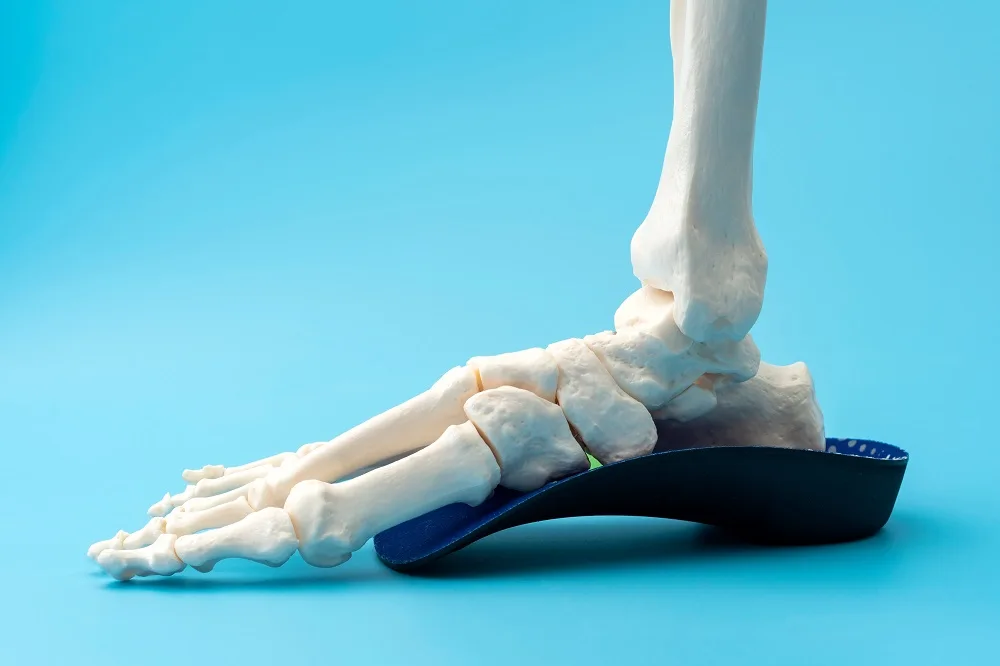

Custom orthotic insoles for leg length discrepancy are the primary non-surgical treatment for structural LLD and provide supportive therapy for functional discrepancies. At PrimeCare, we specialize in creating precisely calibrated orthotic solutions tailored to each individual's specific needs.

Understanding Orthotic Lifts

How do insoles for leg length discrepancy work? They add height under the shorter leg to level the pelvis, realign the spine, and normalize gait patterns. The amount of lift required depends on the measured discrepancy and how well your body has already adapted to the difference. Keep in mind that the prescribed lift height doesn't always equal the measured anatomical difference—providing the full measured discrepancy immediately, especially in long-standing cases, can be poorly tolerated and create new problems.

For discrepancies under 10mm, a full-length orthotic insole for the shorter leg with built-in heel elevation often suffices. These fit inside regular shoes with adequate depth and provide lift, along with arch support and cushioning.

Heel lifts or heel orthotics for leg length discrepancy, ranging from 4mm to 15mm, can be added inside shoes under the existing insole or combined with custom orthotics for a greater total lift. These are especially helpful for fine-tuning or temporary adjustments.

Research and clinical experience reveal that full-length insoles for shorter leg correction provide superior outcomes compared to heel-only lifts for moderate to large discrepancies. Full-length orthotic insoles for leg length discrepancy offer support throughout the entire foot, maintain proper arch position under the added weight of the lift, and distribute pressure more evenly. Heel lifts alone can create a forward pitch, increasing forefoot pressure and causing metatarsal pain, especially with heights exceeding 6-8mm.